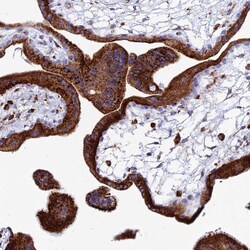

- Submitted by

- Invitrogen Antibodies (provider)

- Main image

- Experimental details

- Immunohistochemical analysis of SPNS1 in human placenta using SPNS1 Polyclonal Antibody (Product # PA5-59813) shows strong granular cytoplasmic positivity in trophoblastic cells.